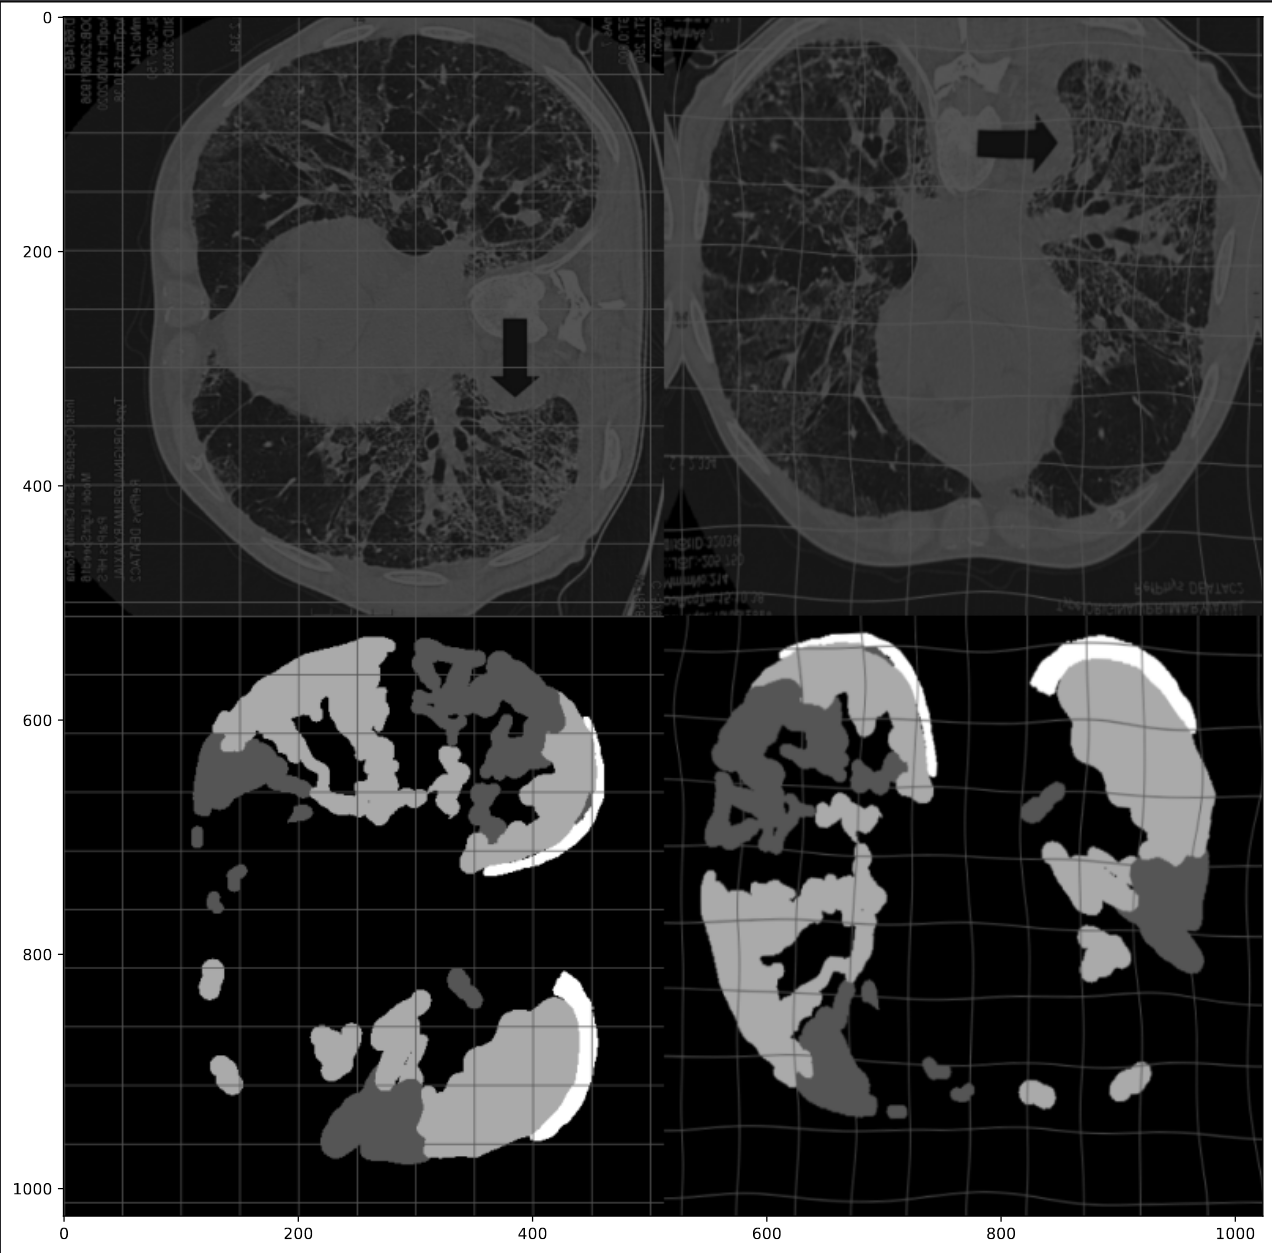

Network outputs during training

Network's outputs on a test image as it undergoes training.